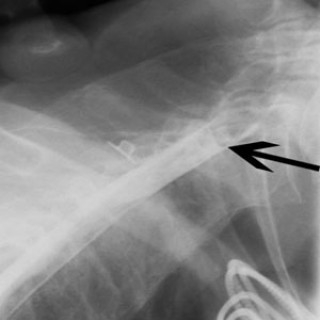

En 23 år gammel førstegangsgravid kvinne som fra tidligere stort sett var frisk, ble innlagt i lokalsykehus ved svangerskapslengde 22 uker + 2 dager, med en seks dagers sykehistorie med generell sykdomsfølelse, feber opptil 40 °C, kvalme, oppkast og anoreksi. I tillegg hadde hun fått økende ansiktsødemer, korsryggssmerter, hodepine og synsforstyrrelser. Svangerskapet hadde vært ukomplisert frem til det aktuelle. Hun var normotensiv. Blodprøvene viste kreatinin 236 µmol/l, karbamid 13 mmol/l, urat 410 µmol/l, leukocytter 15,0 · 10⁹/l, CRP 106 mg/l og trombocytter 86 · 10⁹/l. Leverprøvene var...